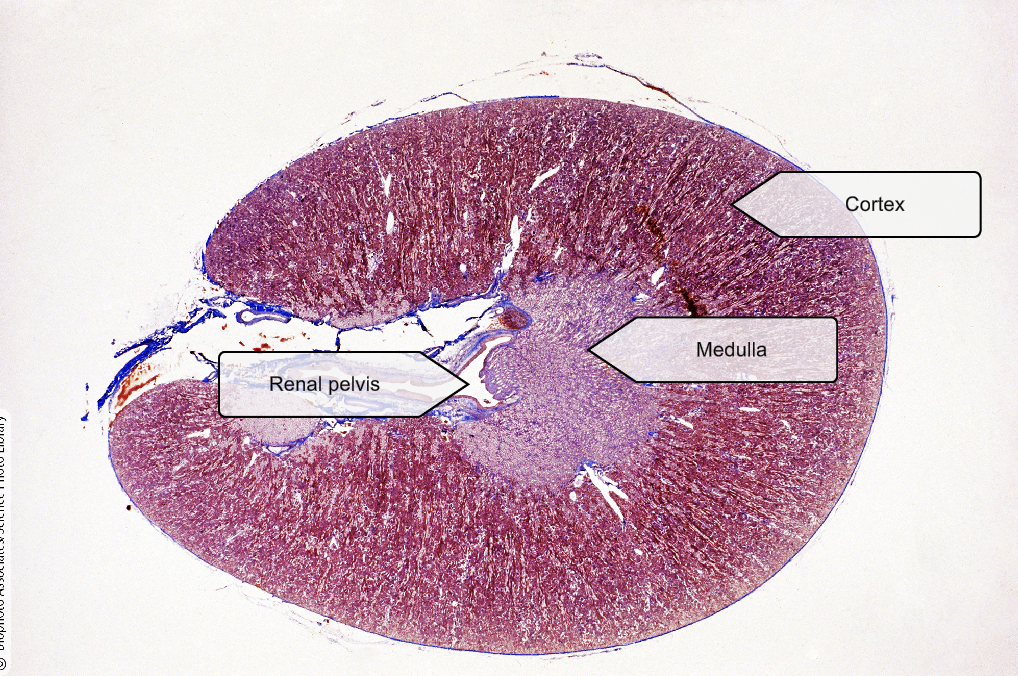

Kidney

Kidney Cortex

Kidney Medulla